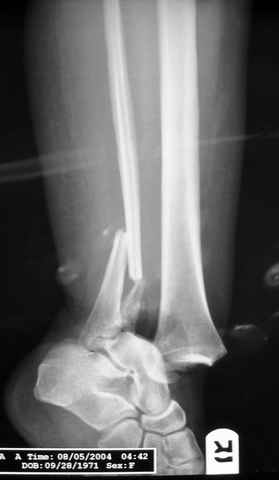

Re: ANKLE FRACTURE

Evgueny Tschekashkin 12 Сентябрь 2004, 15:08

I would suggest to fix the fibular fracture at the very beginning and under fluoroscopical control and axial traction try to restore articular surface stabilizing percutanously by K wires and cannulated screws, type of external fixation to be used is up to your preference.

As I mentioned before (down), in Dr. Salvi's case, I am for temporary fixation, sparing even the talus (not to get wire as possible vehicle for contamination) and than early fusion.

Fixing the fibula, will provide some stability to the ankle and through the incision relatively far from the major zone of injury (antero-medial), and if we do want to restore the anatomy (if feasible), that is the first step - as T. Rüedi told us a long time ago.